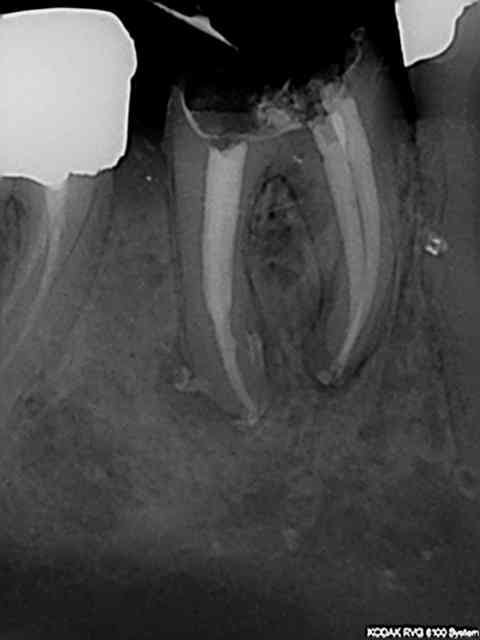

Une de plus. Terminée en down pack + thermo compaction. Tenon à réaliser dans la racine mésiale, j'y vais un peu fort des fois.-))

Chouette endo. Jolis petis puffs sur les canaux accessoires de la racine distale. Elle a eu un peu chaud dans la courbure inter radiculaire mais peste, il faut ce qu'il faut:).